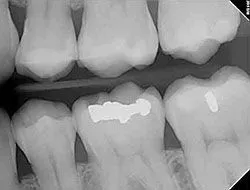

Digital X-rays

Digital X-rays provide several advanced imaging options designed to save time, provide clearer dental photos, and expose patients to less radiation than traditional X-ray technology.